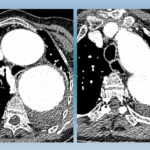

Aggravation progressive d’une difficulté respiratoire chez un patient fragilisé par des infections respiratoires chroniques